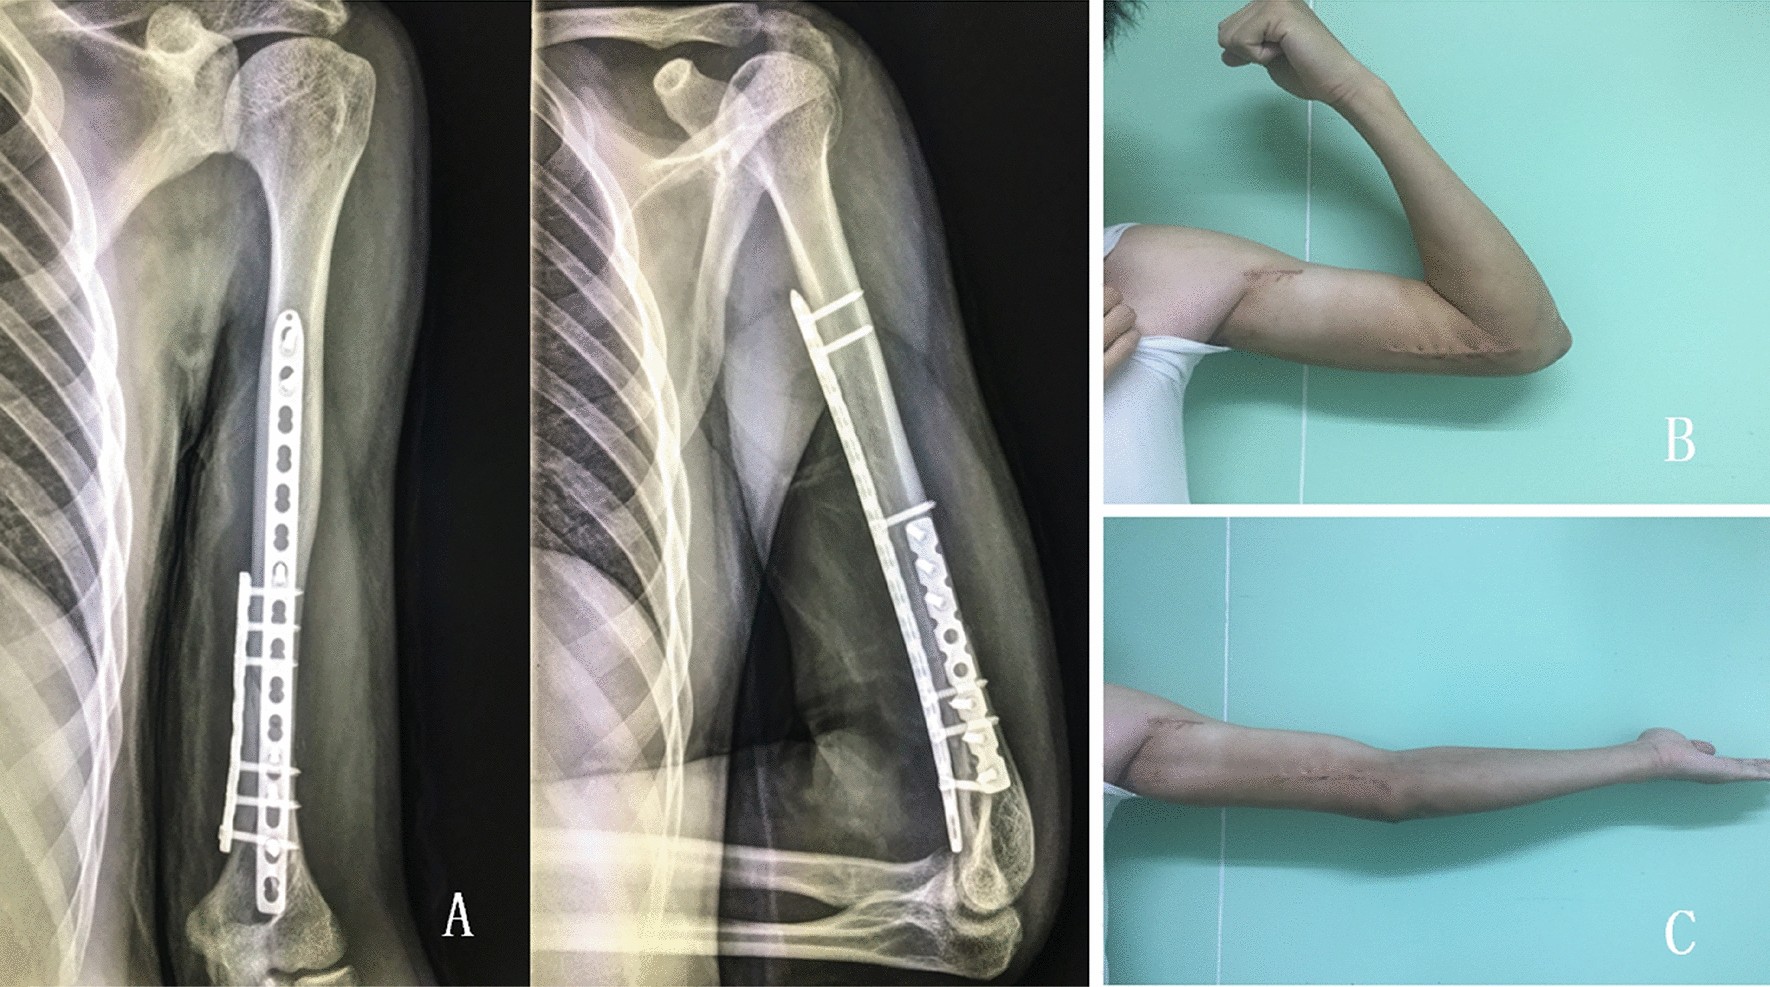

Figure 4

Clinical and radiological outcomes of a patient with distal third diaphyseal fracture of humerus. (A) The final follow-up X-ray; (B,C) the range of motion at the final follow-up of a 34 year-old male was shown.